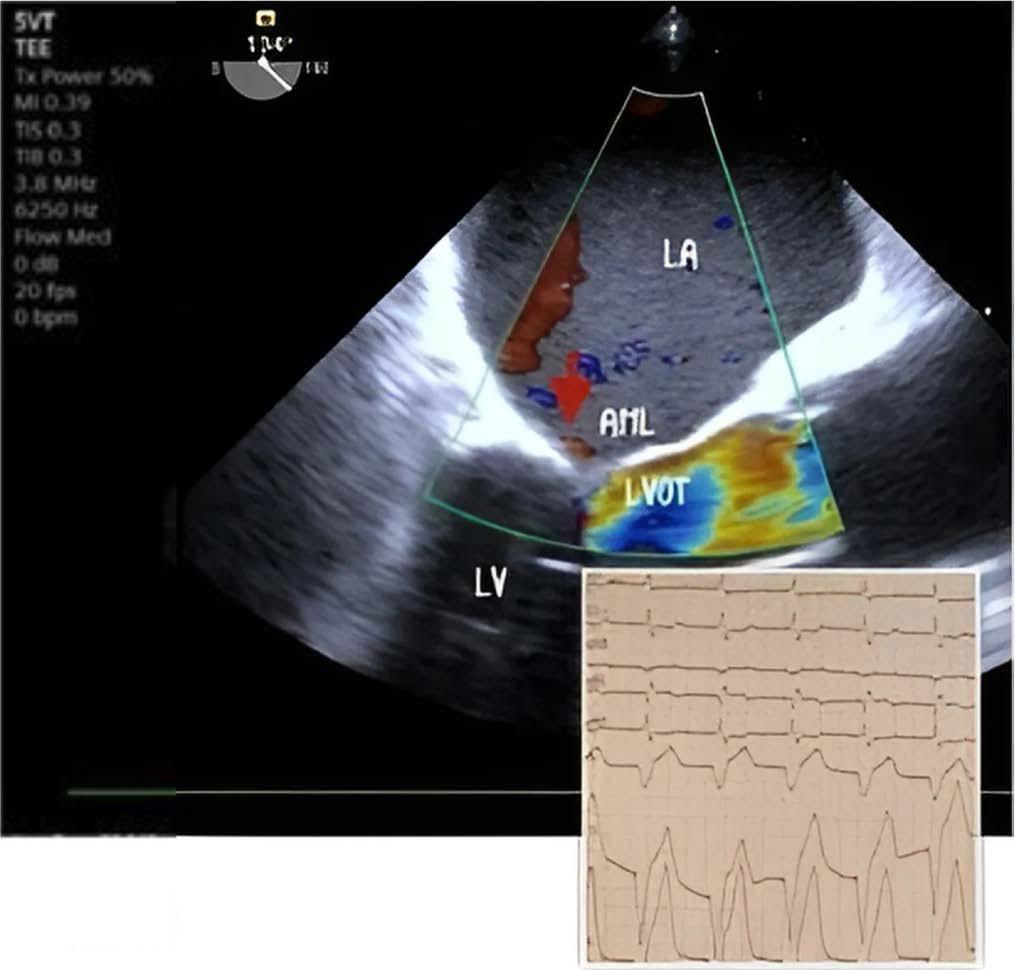

Following this, intravenous nitroglycerin was discontinued, and intravenous fluids along with noradrenaline were administered, but there was no notable improvement in saturation over the next 20 minutes. Correction of bradycardia and optimization of preload and afterload failed to resolve SAM and MR. Consequently, a temporary right ventricular (RV) transvenous pacing was implanted via the right subclavian vein (ventricular pacing frequency 90 bpm) in the ICU. This intervention led to a rapid improvement; MR severity decreased from severe to mild, no LVOT obstruction and good urine output was noted within five minutes. Figure 3

Reverse of mitral regurgitation after temporary Pacemaker implantation. LA left atrium, LV left ventricle, LVOT left ventricular outflow tract, AML anterior mitral leaflet